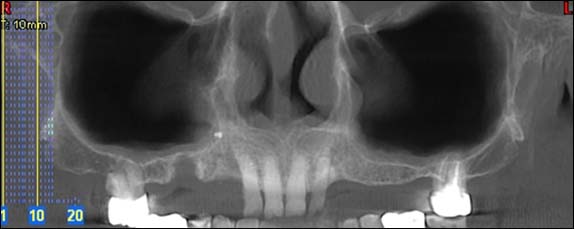

Examens tomographies volumiques type Scanner ou Cône beam

Dernière technologie à notre disposition, cette technique permet de voir en 3 dimensions des images de votre bouche et de mettre en évidence des pathologies ou des anomalies que les autres techniques ne permettent pas d’objectiver.

Coupe axiale

Reconstruction panoramique

Reconstruction coronale